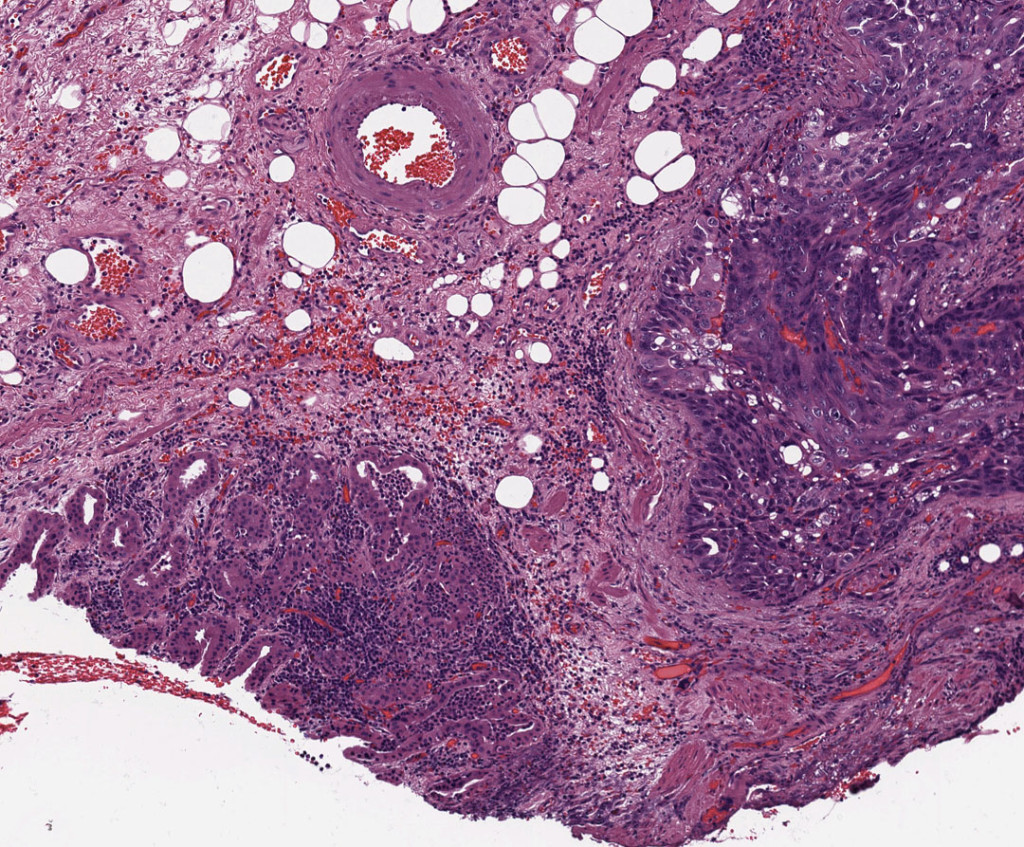

Gastric Cancer Risk Diagnosis and Prevention in Subjects with

Gastric Cancer Risk Diagnosis and Prevention in Subjects with Lab Test For Gastric Cancer If the doctor identifies any abnormal areas in the stomach lining. — learn about the procedures, lab, blood, imaging tests and scans used to help your doctor detect, diagnose and. — tests for diagnosing stomach cancer can include upper endoscopy, biopsy, and imaging tests. upper endoscopy (also called esophagogastroduodenoscopy or egd) is the test most often done. Lab Test For Gastric Cancer.